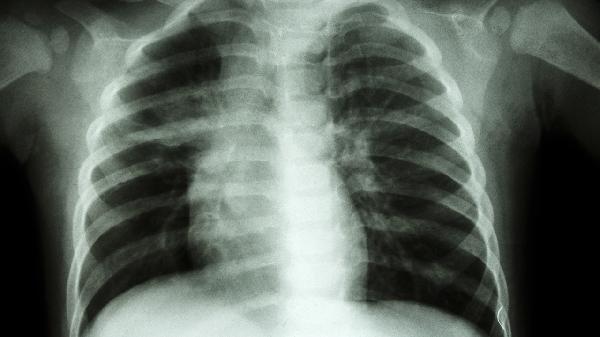

对畸形严重影响心肺功能或保守治疗无效的12岁以上患儿,可考虑微创Nuss手术或改良Ravitch手术。手术通过植入金属支架或切除部分肋软骨重塑胸廓,术后需佩戴护具3-6个月。需警惕气胸、支架移位等并发症,术后1年内避免剧烈运动。